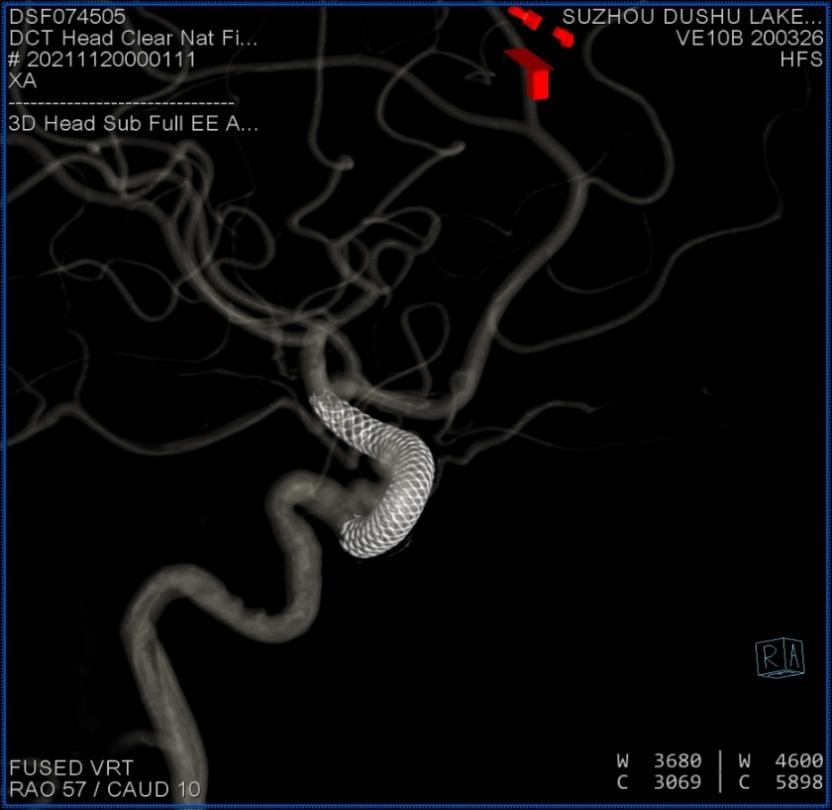

术中Dyna CT提示支架释放良好

术中影像融合提示支架贴壁良好